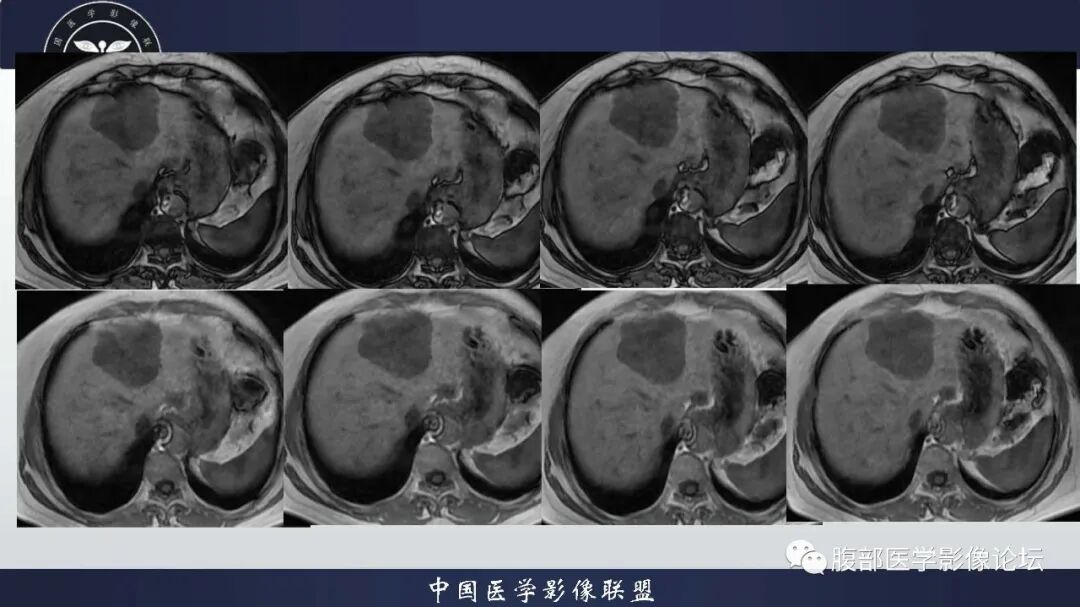

肝脏转移瘤影像病例及鉴别诊断

图片尺寸1280x720